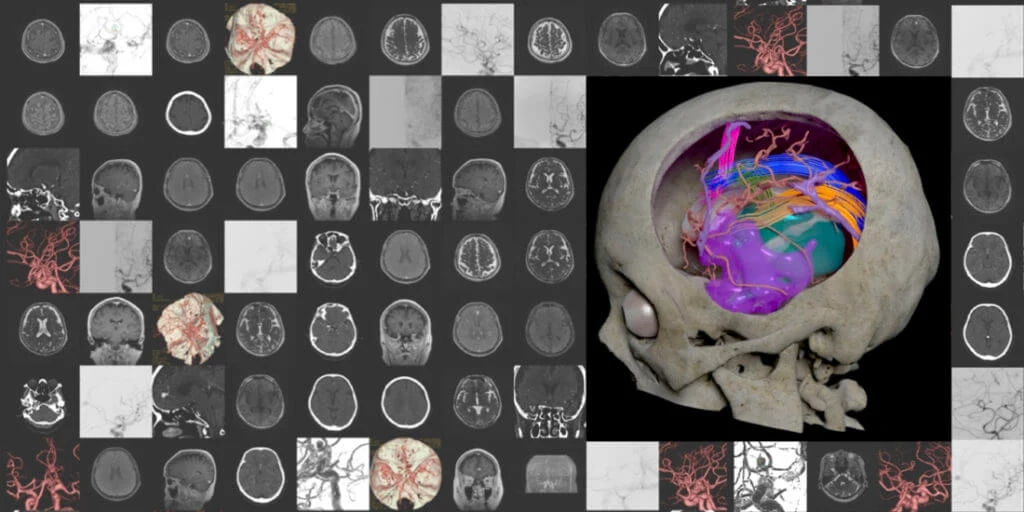

医用画像をそのまま使った診断用の画像 (左) と、手術シミュレーションに使うために色分けがされた画像 (右)

建築や製造の世界では長い間、限られた数の2次元図面から対象物を3次元的に理解する、いわゆる「図面を読む」スキルが必須であるとされてきた。だが昨今は3Dモデルによる可視化が、まさに別次元の理解を提供するようになった。CTやMRIなど、2次元で提供される医用画像をもとに診断や手術が行われてきた医療の世界も、大きな変革の時を迎えている。

「医用画像からCGを作る過程で、どうしても主観や恣意性が入ります。でも医師の間では、医用画像は聖域のようなものであり、皆が見るような映像に自分の考えを入れるべきでないという考え方が主流でした」と、金氏は当時を思い起こす。「例えば動脈を赤、静脈を青で色分けする際、青いところは私が静脈だと判断した部分です。でも、そうした判断は医師が頭の中でのみ行うべきことで、医用画像の切り貼りや色付けは、医療として危険なことだと言われました」。

医用画像の解像度は、現在も512×512ピクセルのモノクロが主流。その中で高精細な画像を実現できたのは、画像処理を行うべき方法が理解できたからだという。「コツは、通常は医用画像を扱わないようなソフトを活用することです」と、金氏。「変形やレンダリングなどは、CGソフトでないとできない。2013年ごろからAutodesk Mayaなどのソフトウェアを使うようになって、途端に画像がきれいになりました」。レンダリングやアニメーション、他のソフトとの連携が行えることにより、診断だけでなく手術シミュレーションが実現。頭の中で組み立てられた手術の手順が、視覚的にも確認できるようになった。